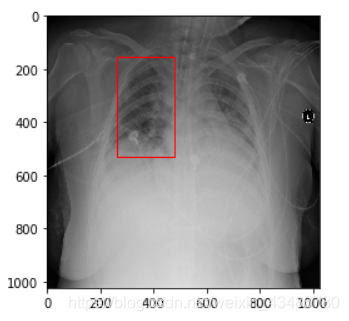

Rectangle((左上角x,左上角y),宽,高)

import matplotlib.pyplot as plt

fig = plt.figure()

ax = fig.add_subplot(1,1,1)

rect = plt.Rectangle((top_left_x, top_left_y), width, height, fill=False, edgecolor = 'red',linewidth=1)

ax.add_patch(rect)

plt.imshow(image_array) # 图像数组

plt.show()

本文介绍如何利用Python的Matplotlib和PIL库在图像上绘制矩形。通过Rectangle函数和ImageDraw模块,可以指定矩形的位置、大小及颜色,适用于图像处理和数据可视化场景。